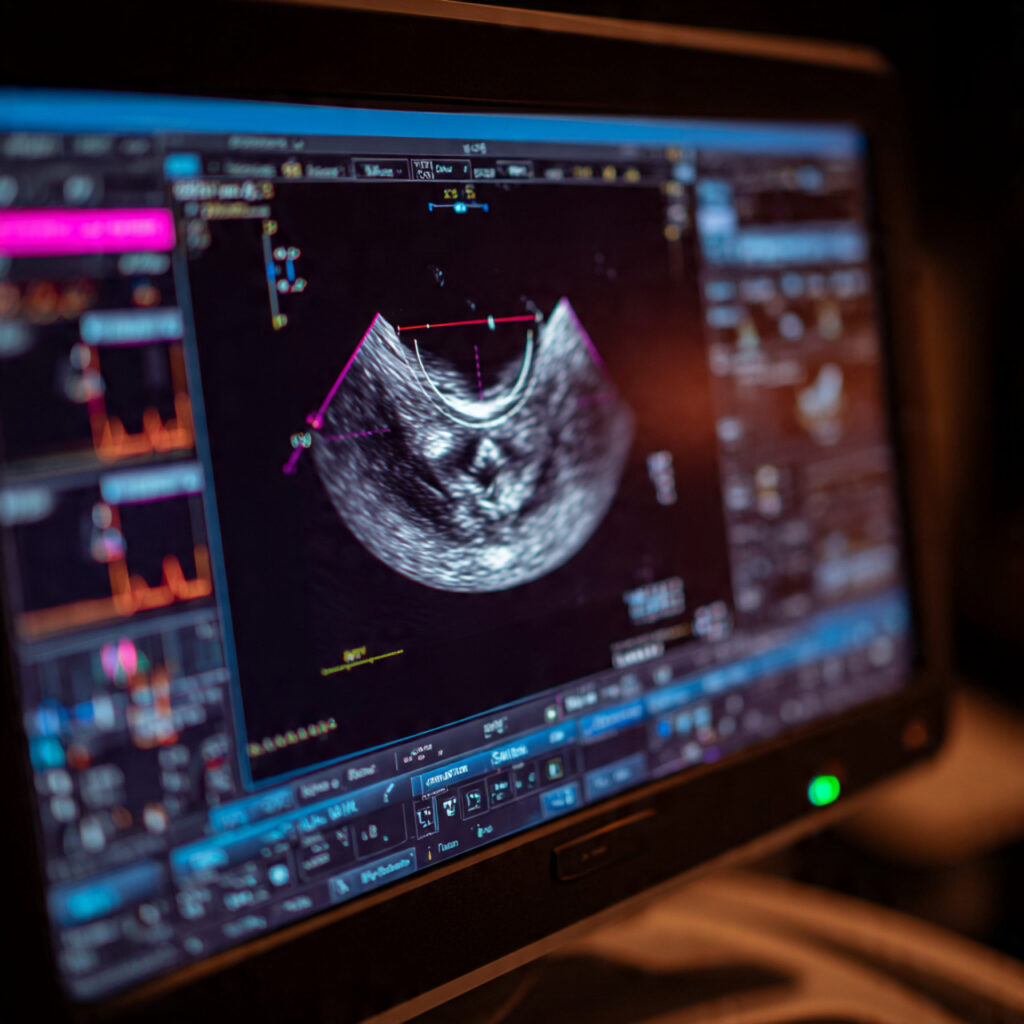

The NT Scan (Nuchal Translucency Scan) measures the fluid-filled space at the back of the baby’s neck. This area naturally contains a small amount of fluid, but if the fluid is more than normal, it may suggest a higher chance of certain genetic or chromosomal conditions.

💡 What Does the NT Measurement Mean?

A normal NT measurement is usually:

👉 Less than 3.0 mm

(Average is around 1.5–2.5 mm depending on crown–rump length)

📍 How Is the NT Scan Done?

The NT scan is like a normal pregnancy ultrasound.

Steps include:

- You lie down on the bed

- The doctor applies gel on your abdomen

- The ultrasound probe is used

- The baby’s neck area is magnified

- Fluid thickness (NT) is measured in millimeters

- A detailed report is generated

No pain, no risk, and no needles involved.

It is a safe and non-invasive scan.